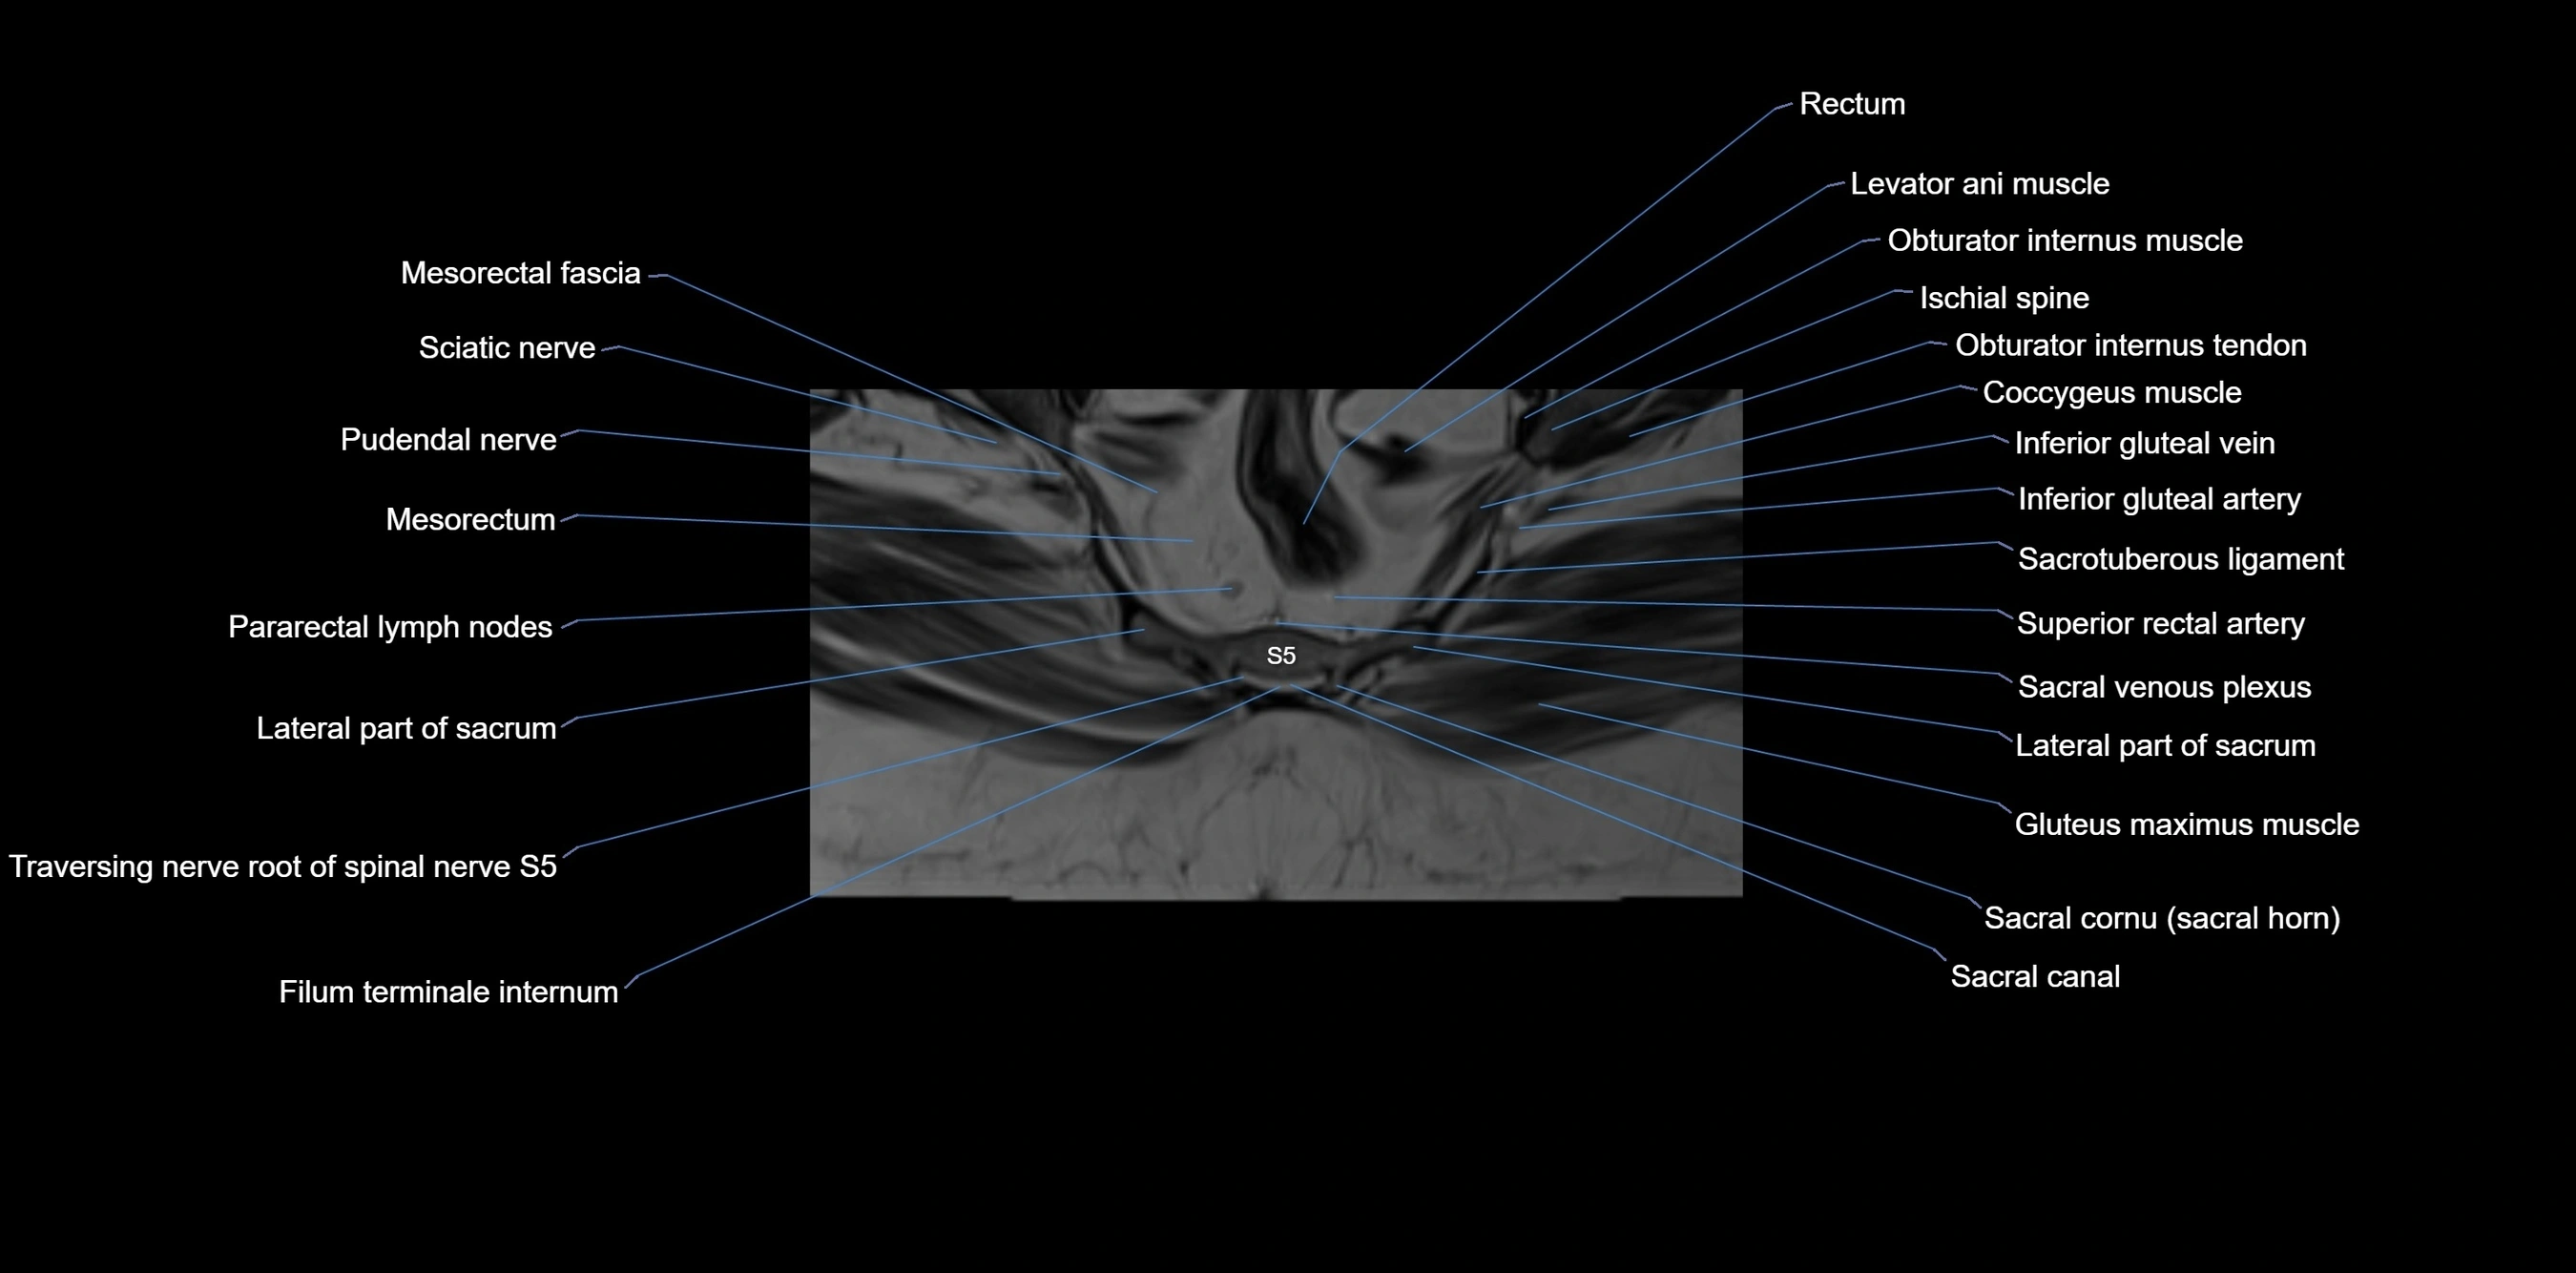

MRI image

image